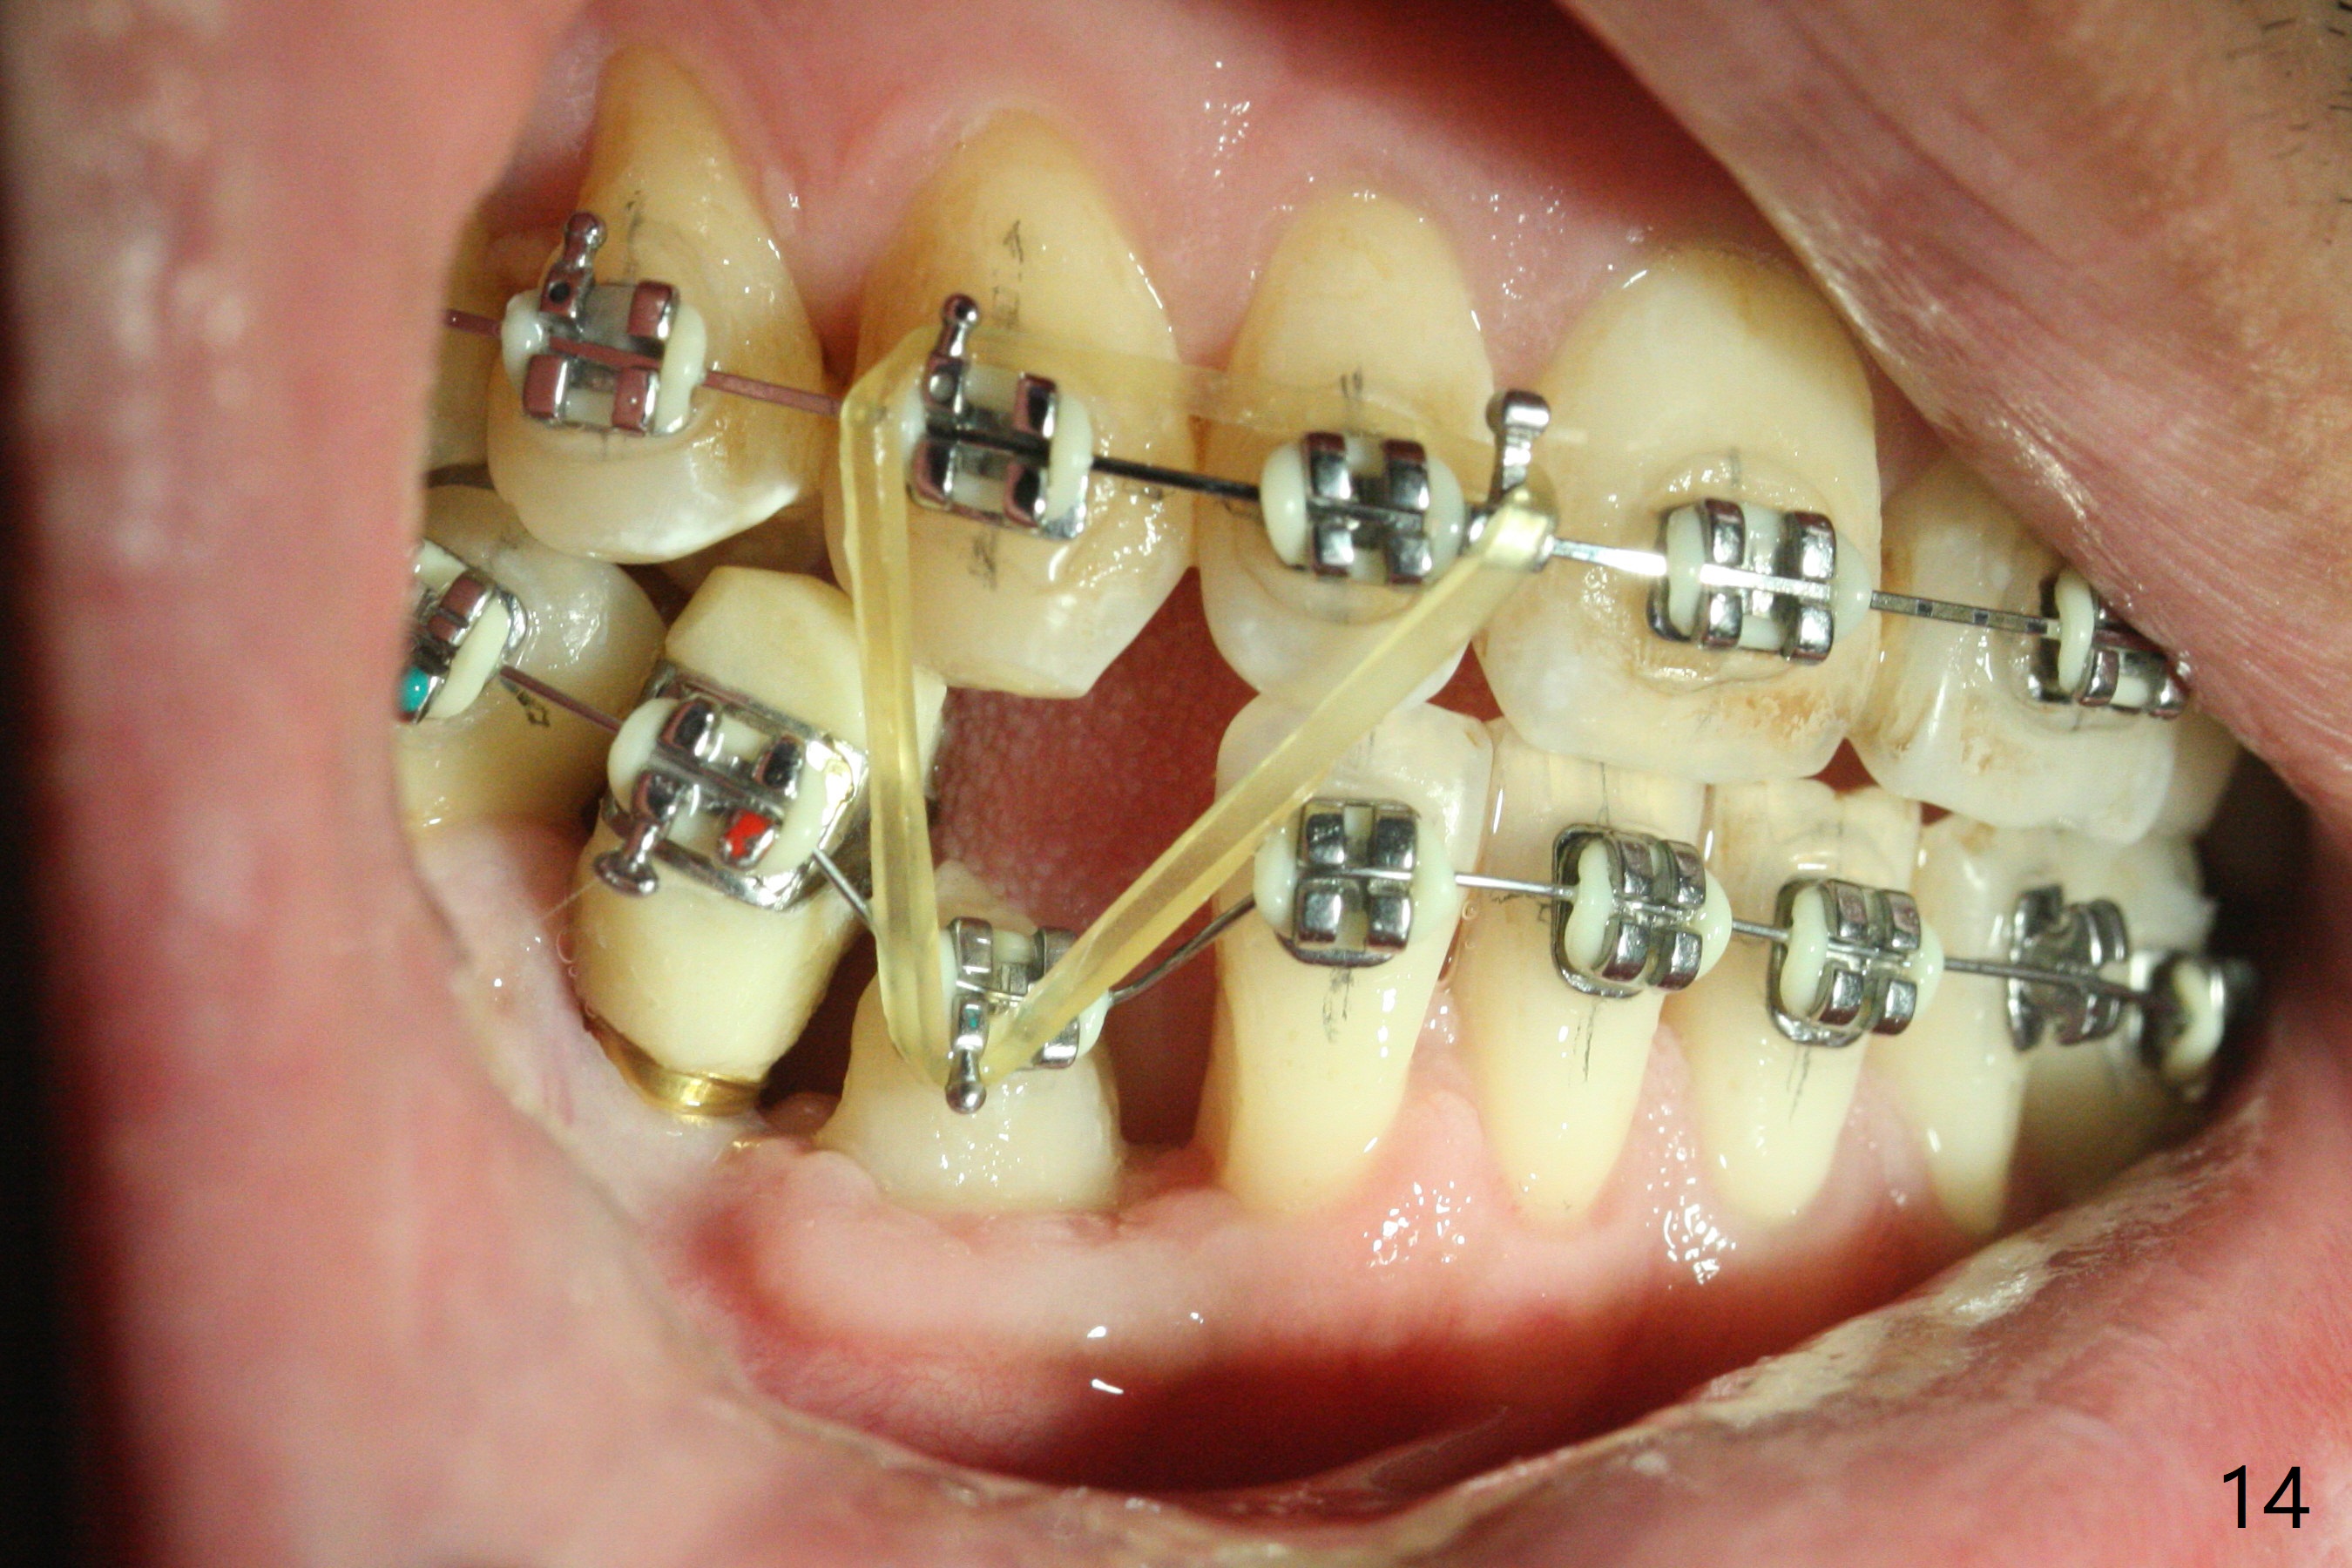

When the surgical guide for #28 is removed, the 4x13 mm implant is found to be superficial and buccal. Part of the buccal mucosa is nonkeratinized. After 1 mm deeper placement of the implant, CT confirms the buccal placement (Fig.1, as compared to design). In fact the guide was doubly checked for fitness prior to osteotomy, but grossly it seemed to be seated properly. The suspicion is related to the trimming at the site of #27 (Fig.2,3 (*), as compared to a mounted model in Fig.4,5 (arrowhead) and the model sent to lab for guide fabrication). The lab agrees to redesign the case. There is a narrow buccal band 1 week postop (Fig.6). The patient is a smoker. The implant was placed buccal (Fig.7, 1 month postop). A new 4x13 mm implant is placed on the top of the 1st line following 3x14.5 mm drill (Fig.8 (35 Ncm)). In fact the implant position is not changed much. Four months post banding (20 ss) and 2 months post 2nd implant placement, the tooth #27 is exposed for bracket; extrusion is initiated (Fig.9). In 3 weeks of retraction, the bracket is supragingival (Fig.10). The canine contacts the distal healing abutment with 2 months of retraction (Fig.11). It seems necessary to initiate lower bracket placement. There is no bone loss 4 months postop (Fig.12). A 4.5x7(4) mm abutment is placed (Fig.13) for a temporary crown as an anchor (Fig.14) to further extrude #27 with continuous inter-arch retraction (to reduce tension upon #26 with severe bone loss (Fig.12)). LR3 extrusion is incomplete, although there is an increase in bone distal to LR2 ~ 10 months of extrusion (Fig.15).